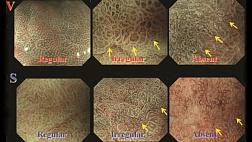

В представленном атласе освящены актуальные методы комплексной эндоскопической диагностики опухолевой патологии дыхательных путей и желудочно-кишечного тракта. Целью данной книги является расширение кругозора врача, знакомство с возможностями современной эндоскопии в онкологии. Атлас снабжен современными классификациями опухолей и предопухолевой патологии, большим количеством цветных иллюстраций, в нем представлены многочисленные уникальные случаи, которые можно встретить в повседневной клинической практике. Обширный авторский опыт будет полезен целевой аудитории. Издание предназначено для эндоскопистов, хирургов, онкологов, пульмонологов, ЛОР-врачей, гастроэнтерологов.